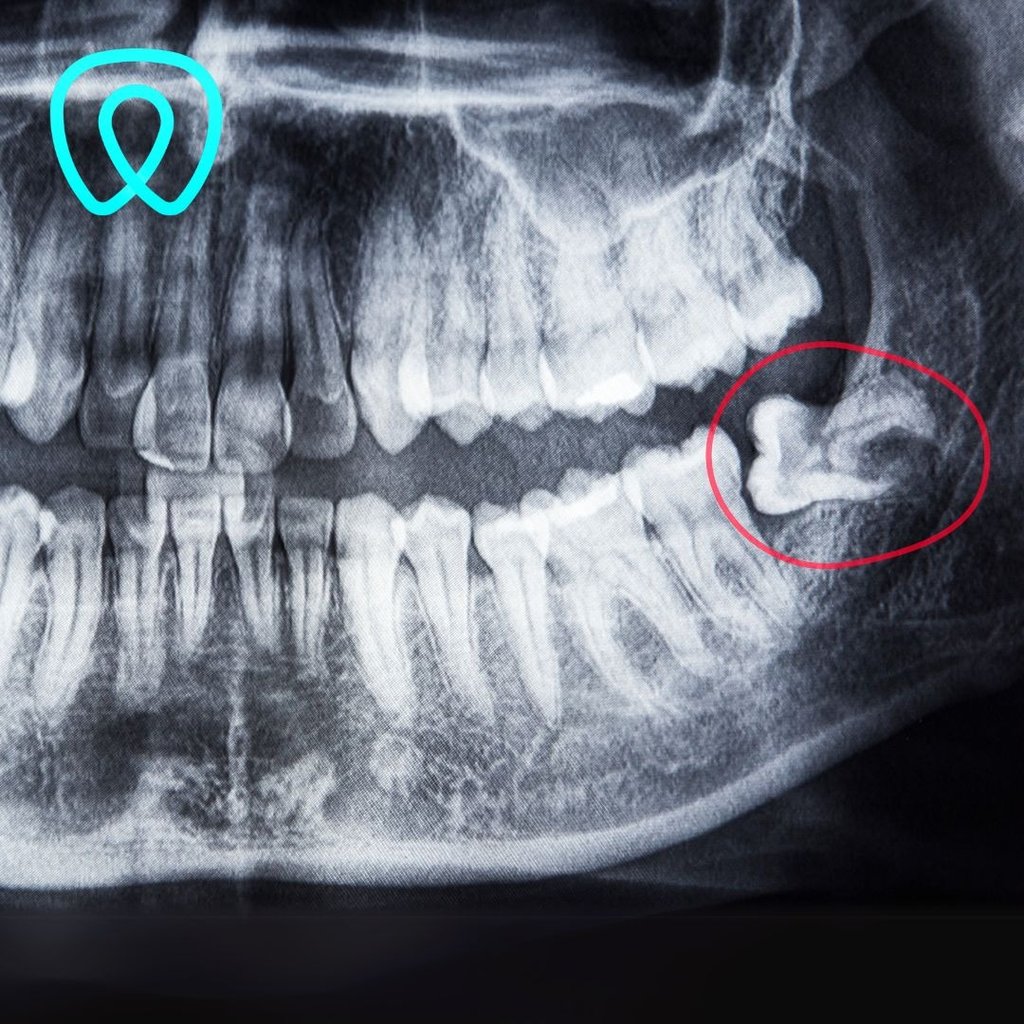

Realizamos procedimientos como extracciones quirúrgicas de terceros molares retenidos, regularización de rebordes óseos, fenestración de caninos, biopsias de lesiones orales, entre otros. Contamos con especialistas entrenados en técnicas mínimamente invasivas, anestesia local o sedación según el caso, y protocolos de bioseguridad rigurosos. Nuestro enfoque combina precisión clínica, control del dolor y una recuperación rápida para nuestros pacientes.

Cirugía maxilofacial